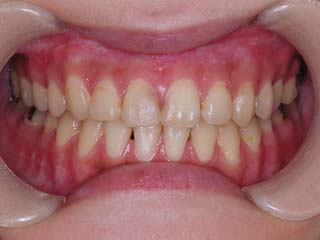

主訴:顎が歪んでいる 下顎が出ている

診断名:骨格性下顎左方偏位を伴う骨格性下顎前突

年齢:28歳

使用した主な装置名:TPB、マルチブラケット装置

抜歯/非抜歯および抜歯部位:抜歯(上顎左右第一小臼歯)

治療期間:動的処置2年3か月、経過観察3年

費用の目安:保険適応 自己負担金として30~50万

リスク、副作用:外科手術によるリスク、マルチブラケット治療に伴う歯根吸収など偶発症が発生するリスクがある。

強い下顎前突と下顎の左方変位がみられます。成長を終了した永久歯列ですので、骨の大きさのズレへのアプローチは大きく別れる所です。程度が小さければ、歯の傾きで補うように解決しますし、大きなズレであれば、外科的に骨のズレを改善する治療が選択されます。前後のズレ、左右のズレと条件が重なってきた場合、より外科矯正での改善が望ましいものとなるでしょう。

一般的な外科矯正治療の流れは、術前矯正・外科矯正・術後矯正・保定治療と移行します。術前矯正では、手術を行う時点で、上下がぴったり合うような歯列に仕上げる事になりますので、逆に言えば、手術をしていない直前においては、とんでもなく噛めない状態となっている事が多いです。このケースでは下顎のみのセットバック(後退術)をSSROにて行いました。